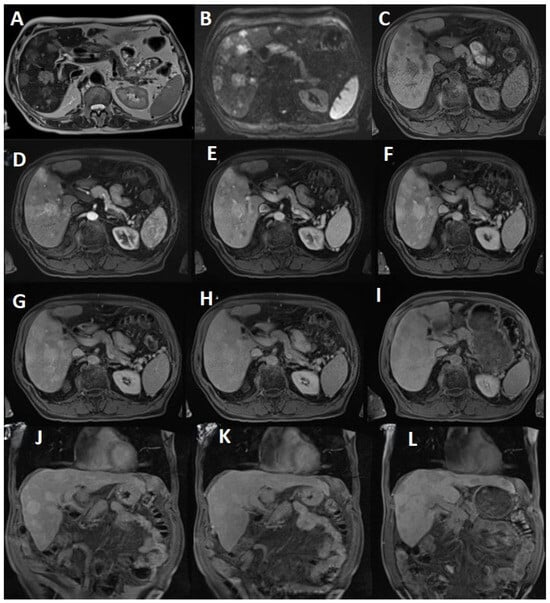

2.2. Standard MRI Liver Protocol

2.4. Delayed Multiphase Scanning